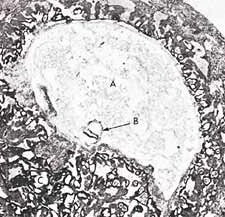

Figure 3: In this photomicrograph, we can see the suspension of an embryo (marked B) during the alaqah stage (about 15 days old) in the womb of the mother. The actual size of the embryo is about 0.6 mm. (The Developing Human, Moore, 3rd ed., p. 66, from Histology, Leeson and Leeson.)